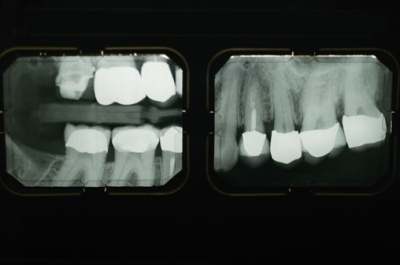

I have been feeling pain in my back tooth for the past couple of days, but I have been ignoring it hoping it goes away or goes somewhere else. With a tooth pain it becomes difficult to concentrate, and the pain I’m having is resulting from pressure. I don’t have a cavity thats for sure, I brush my teeth about 4 times a day, and I’m not much of sweets person. Its the pressure that hurts, and I’m delaying the trip to the dentist as much as possible, but at one point I’m going to have to go.

I don’t have a specific dentist that I go to in Kuwait, since I have run into problems with different dentists and sometimes they really screw up. At one point I didn’t go to a dentist for four years until I had to in the states, and to my luck I stumbled upon a fantastic compassionate dentist. But here I’m going to try my luck with one dentist maybe next week, it all depends how much pain I feel over the next couple of days. I’m very stubborn when it comes to the dentist.